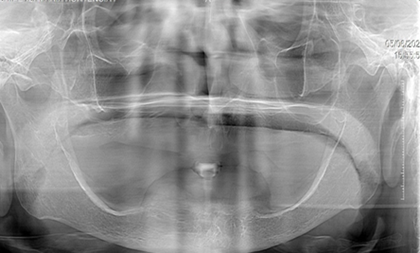

Fotografía del maxilar inferior (Figura 1).

Figura 1. Maxilar Inferior.

Elaboración: Los autores.

La paciente lleva usando una prótesis 10 años, debido a la irregularidad de rebordes que presenta la mandíbula, se considera desde el punto protésico un caso deficiente.

EXAMEN RADIOGRÁFICO

Paciente presenta elevaciones irregulares en el maxilar inferior (Figura 2).

Figura 2. Radiografía del maxilar inferior.